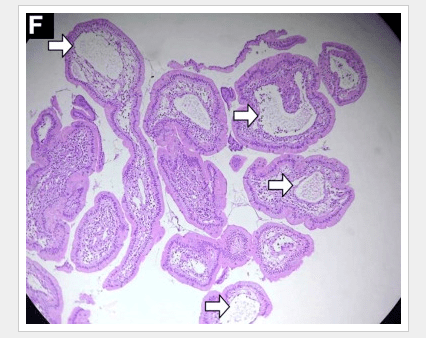

“Histologic examination shows chronic inflammation of the ileum characterized by increased lymphoplasma cell infiltration of lamina propria without malignancy. Moreover, marked dilatation of lymphatic ducts that involved the mucosa was identified (Figure F)… a diagnosis of primary intestinal lymphangiectasia (PIL) was made.